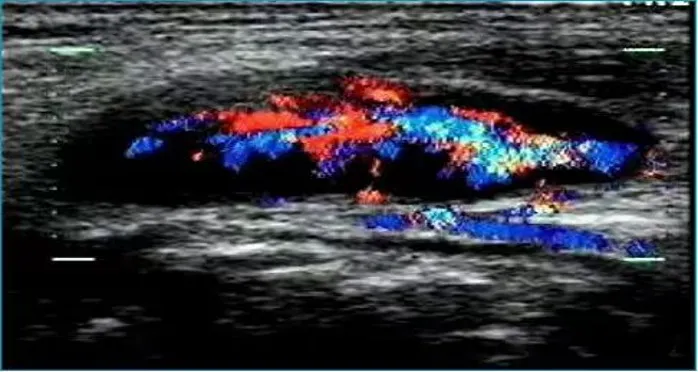

病例:右侧颈部肿痛3天,颈部可触及多个痛性结节。

超声描述:右侧颈部Ⅲ、Ⅳ区可见多发肿大的淋巴结,大者约21x6mm,呈椭圆形,皮质增厚,髓质居中,内部血流信号明显增多,呈放射状分布。